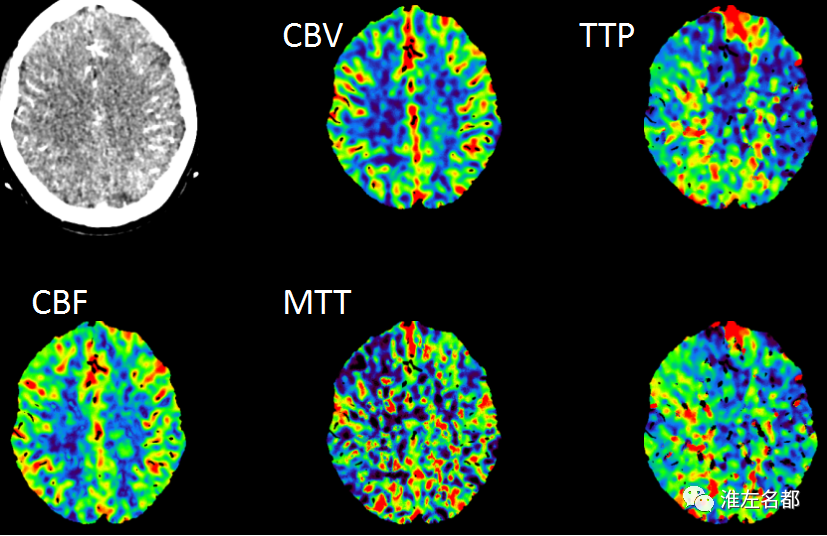

△脑CTP:左侧大脑前动脉区TTP较对侧显著延长,但其大部分区域CBV和CBF未见明显降低。

1.最后表现正常-到院时间达7小时余,超出静脉溶栓时间窗。2.NIHSS-14,左侧大脑前动脉闭塞,其供血区TTP较对侧显著延长,但其大部分区域CBV和CBF未见明显降低,提示较大范围“组织窗”,可考虑急诊血管内治疗。